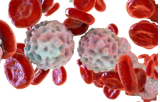

Kanker is een ziekte die gekenmerkt wordt door de ongecontroleerde proliferatie van cellen als gevolg van genetische mutaties die de normale celcyclus verstoren. In tegenstelling tot normale cellen verliezen kankercellen hun vermogen om te reageren op signalen die de celgroei en -deling reguleren en krijgen ze de capaciteit om zich oneindig te delen. Deze gemodificeerde cellen vermenigvuldigen zich ongecontroleerd en vormen tumoren die omliggend weefsel kunnen binnendringen en vernietigen. Bovendien kunnen kankercellen zich losmaken van de oorspronkelijke tumor en zich verspreiden naar andere delen van het lichaam, een proces dat metastase wordt genoemd. Onderscheidende kenmerken van kankercellen zijn onder andere hun vermogen om aan geprogrammeerde celdood te ontsnappen en de vorming van nieuwe bloedvaten op gang te brengen om hun toevoer van zuurstof en voedingsstoffen veilig te stellen. Deze kenmerken maken kanker tot een complexe en multifactoriële ziekte die een grondig begrip van de mechanismen vereist om effectieve behandelingsstrategieën te kunnen ontwikkelen. Kortom, kanker is het resultaat van de progressieve transformatie van normale cellen in kankercellen, die hun controle over groei en deling verliezen en het vermogen krijgen om uit te zaaien, waardoor de gezondheid van het organisme wordt bedreigd.